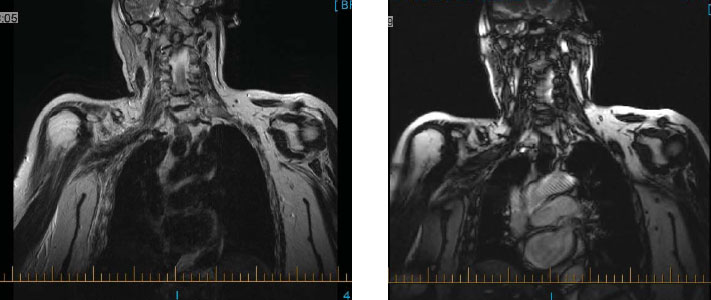

RÉSONANCE MAGNÉTIQUE

PLEXUS BRACHIAL AVEC INJECTION DE GADOLINIUM

Importante zone en placard de tissu anormal dont les contours sont légèrement nodulaires qui infiltre l'ensemble du plexus brachial de la région supra-claviculaire jusqu'à la région axillaire, sur 9 à 10 cm, impliquant les différents troncs du plexus brachial jusqu'à l'origine des nerfs périphériques du membre supérieur droit. De façon secondaire, on observe une atrophie de dénervation de la musculature péri-scapulaire. Dans le contexte clinique, l'aspect est tout à fait compatible avec une atteinte métastatique du plexus brachial chez cette patiente opérée pour une mastectomie droite, il y a plusieurs années.